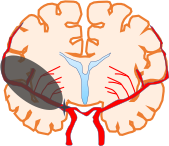

脳梗塞は脳につながる血管がつまり、脳細胞が死んでしまう病気です。突然起こるもの、前触れがあり段階的に悪化するもの等があります。

脳梗塞は原因によって血栓性、血行力学性、塞栓性に分類されます。

原因による分類の他にも、臨床型分類といわれる脳梗塞の臨床像を元にした分類の仕方があります。原因、臨床病型に合わせた治療を行います。